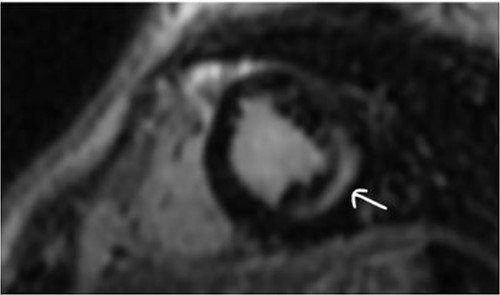

Clinically, both patients complained of worsening palpitations over the last few months with no associated dyspnea or tiredness. A Holter examination recorded 14 444 VES and 212 NSVT, with very similar results in both sisters. The echocardiography revealed a myxomatous Barlow mitral valve with anterior and posterior leaflet prolapse and two regurgitant jets resulting in moderate to severe mitral valve regurgitation as well as mitral annular disjunction in both cases (Figs 1 and 2). A cardiac MRI on a 3 T Lumina Siemens revealed at the mid-left ventricular level, a midwall fibrosis in the midlateral myocardium (Figs 3 and 4) and confirmed a mitral annular disjunction of 12 mm (Figs 5 and 6). Additional findings included a dilated LV with mildly depressed contractility, no visible myocardial scarring, no structural heart disease and a normal sized RV with mildly depressed contractility.